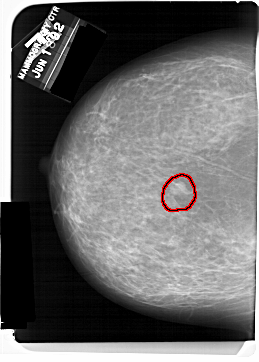

A_1560_1.RIGHT_MLO

RIGHT_MLO LINES 6346 PIXELS_PER_LINE 4891 BITS_PER_PIXEL 12 RESOLUTION 43.5 NON_OVERLAY

FILE: A_1560_1.LEFT_MLO.OVERLAY

TOTAL_ABNORMALITIES 1

ABNORMALITY 1

LESION_TYPE MASS SHAPE LOBULATED MARGINS OBSCURED

ASSESSMENT 4

SUBTLETY 4

PATHOLOGY BENIGN

TOTAL_OUTLINES 1

BOUNDARY